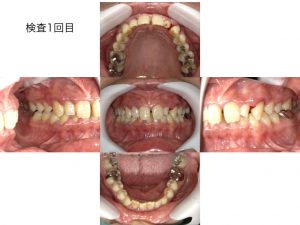

初診時の写真です。

歯茎の中に歯石が確認できます。

歯茎に触れていない状態でも出血しています。